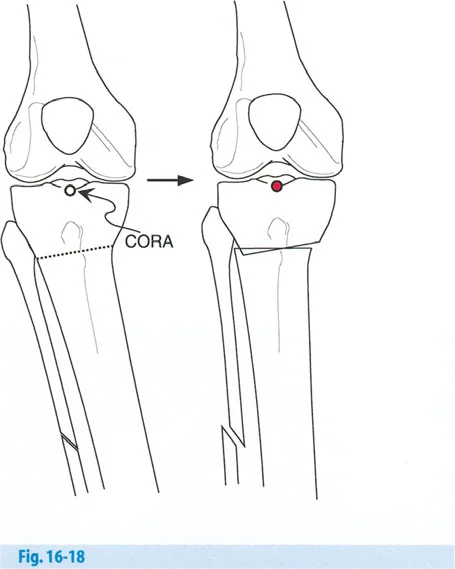

- تحديد مستوى مركز الدوران الفعلي للزاوية (CORA): لتجنب التشوه الترجمي الثانوي، يتم مطابقة مركز الدوران الفعلي للزاوية (ACA) مع مركز الدوران الفعلي للتشوه (CORA) قدر الإمكان.

- قطع العظم الوتدي الإغلاقي (Closing Wedge Osteotomy): يتم إزالة إسفين من العظم.

- قطع العظم الوتدي الفاتح (Opening Wedge Osteotomy): يتم فتح فجوة في العظم وتثبيتها بلوحة ومسامير، وقد تتطلب ترقيعًا عظميًا.

- قطع العظم الوتدي المحايد (Neutral Wedge Osteotomy): يتم إزالة إسفين من جانب وإعادة زرعه في الجانب الآخر.

- قطع العظم القبو البؤري (Focal Dome Osteotomy): يمكن تعديله لشد الرباط الجانبي الإنسي (MCL) إذا لزم الأمر.